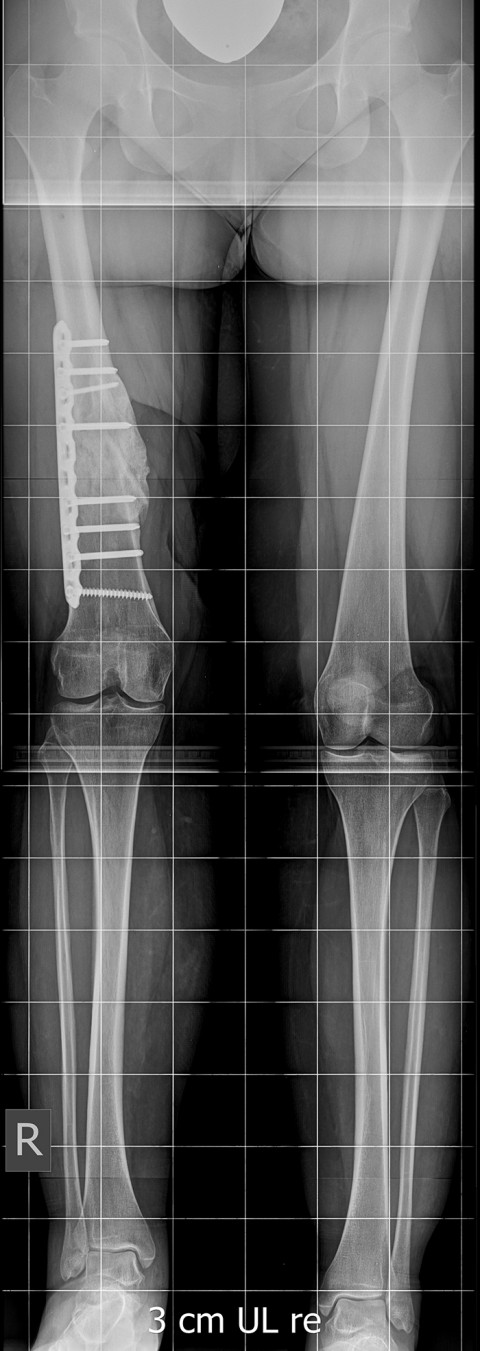

Aufgrund der komplexen Deformität mit zeitgleich vorliegender Beinlängendifferenz von -3.5 cm am rechten Oberschenkel (als Folge des ausgeprägten Knochendefektes durch die Zertrümmerung des Oberschenkelknochens) wurde die Patientin bei uns vorstellig.

Gemeinsam mit der Patientin entschieden wir, zunächst den Nagel zu entfernen und den Oberschenkel im Bereich der Pseudarthrose zu stabilisieren, um gleichzeitig mit der Verheilung des Knochens auch die Achse korrigieren zu können. Dies gelang erfreulicherweise unkompliziert, es blieb jedoch die ausgeprägte Beinlängendifferenz aufgrund des um 3.5 cm verkürzten Oberschenkels (Bild 2).